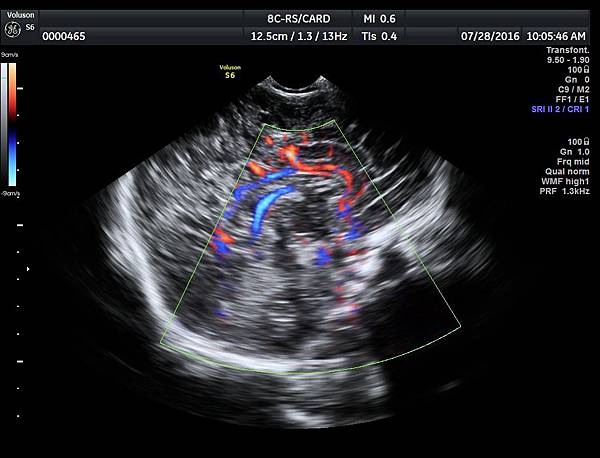

附上2016年7月28日我在診所幫一位一個半月的嬰兒照的腦部超音波,經由前囟門進入,駢胝體可以很容易的被完整看到,參考附圖15~16。